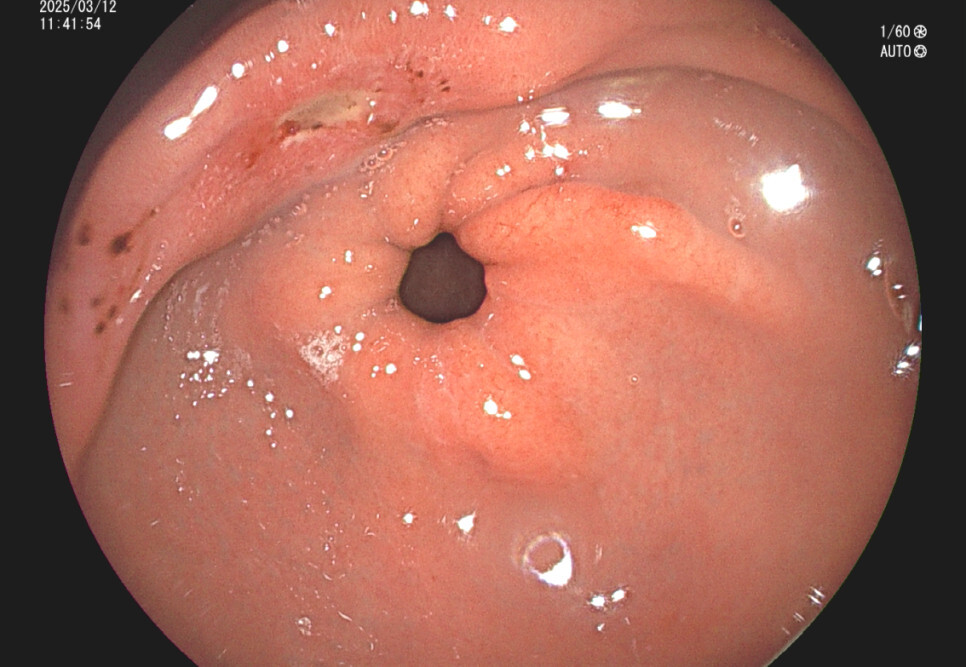

위궤양의 내시경 소견 증례입니다.

사례 1.57세 남성, 기상 후 입이 쓴 증상 주소로 내원